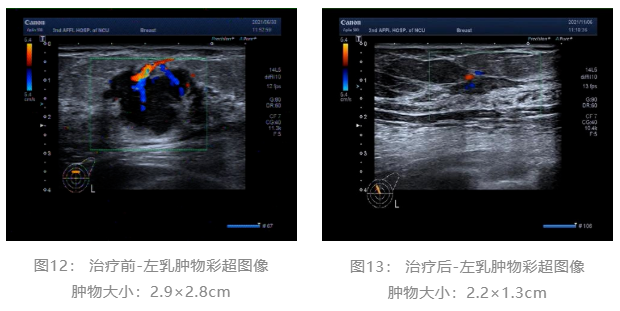

乳腺彩超:

术前评估:新辅助治疗期间患者无明显不适,一般状况可。新辅助治疗后左乳房肿瘤及腋下肿大淋巴结退缩明显,疗效评估PR,未发生不良事件,择期可行左乳癌改良根治术。